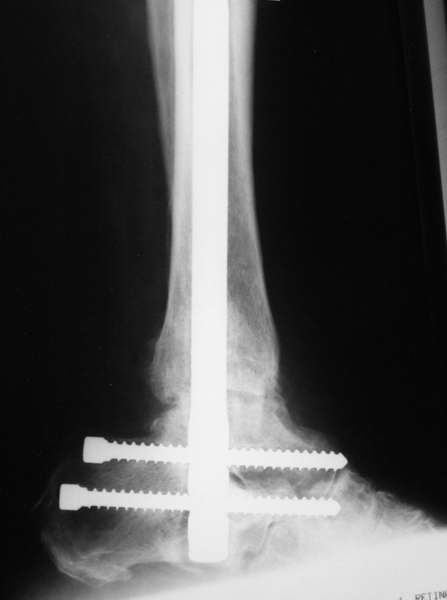

Мы бы сделали тоже самое с остатками лодыжек, но артродез, который безусловно показан, выполнили бы закрыто блокируемым штифтом (типа DFN) через пятку. Опороспособность восстановится сразу, артродез (рентгенологический) наступит месяцев через 4-6.

С уважением, А.Семенистый.

Да. Изначально планируется и подтаранный артродез.

Можно: 65-летняя пациентка, оперирована по поводу несросшегося в гипсе перелома лодыжек с патологической вальгусной установкой стопы и выраженным нарушением опрной функции. Оперирована через 6 месяцев после травмы. Рентгенограммы через 4 месяца после операции.

Само формирование и рассверливание канала для штифта и есть те "отдельные мероприятия", которых достаточно...